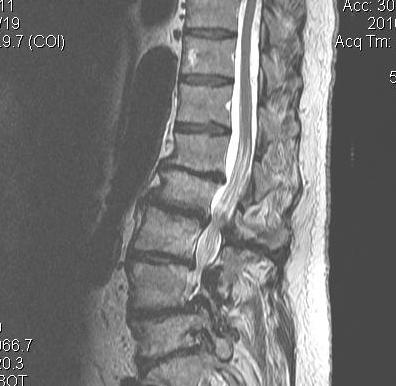

MRI

Myelopathy

Decreased height of nerve foramina